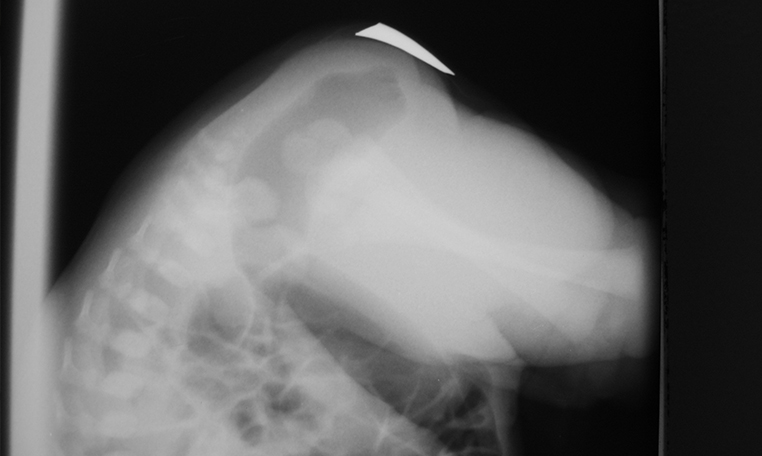

Ano Imperforado